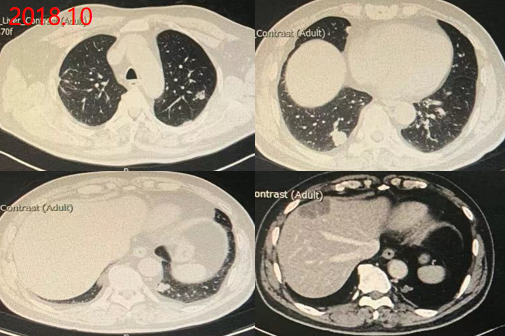

2018.11复查疗效评价PD

2018.10: